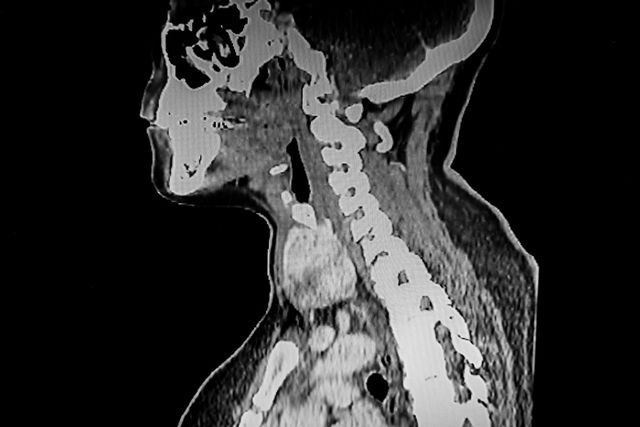

기사의 이해를 돕기 위한 사진 / Jo Panuwat D-shutterstock.com